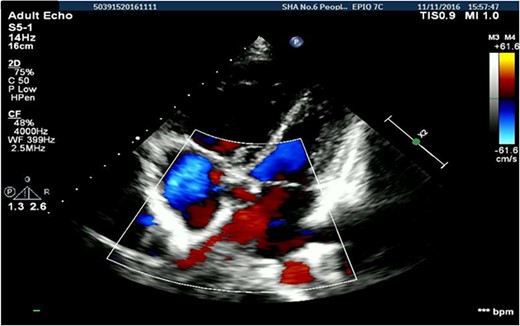

A 26-years-old woman comes to the hospital because of a 1-week history of fatigue. She has no history of serious illness and cardiovascular examination history. She can do light to moderate physical activity without developing dyspnea. Vital signs are within normal limits. Cardiac auscultation shows a heart murmur at the second intercostal space on the left sternal border and a wide-split S2 that does not change with respiration. Physical examination shows no bluish-colored lips or digital clubbing. The transthoracic echocardiography indicated atrial septal defect (Type II, diameter 25 mm); left-to-right bidirectional shunt, severe pulmonary hypertension (estimate PAP: 114 mmHg); right atrium and ventricular dilatation with severe tricuspid regurgitation (Fig. 1). Blood gas analysis showed: PH: 7.36, PaO2: 77.2 mmHg and PaCO2: 36.1 mmHg. The electrocardiogram was normal. Chest radiograph demonstrated pulmonary artery segment bulging suggesting severe PH. Right-heart catheter verified severe PH (PAP: 112 mmHg). Therefore, repair or closure of the ASD would be a high risk of developing a probable surge of pulmonary artery pressure. After serious consideration, we decided to treat her with a manual fenestrated closure device. Under general anesthesia and transesophageal echocardiography (TEE) guidance, the patient has inserted a handmade fenestrated Amplatzer Septal Occluder (reserved hole 5 mm, Abbott, St. Paul, MN, USA; Fig 2) through the right femoral vein, occlusion of the occluder in advance. After the device was released, TEE showed a slight left-to-right shunt. After the procedure, the patient’s oxygen saturation was 100%. On the second day after surgery, this patient was discharged. Echocardiography was performed in the second month and sixth month since discharge, and the PAP was 68 and 34 mmHg, respectively. Meanwhile, tricuspid regurgitation was reduced to mild. The right atrium and right ventricle size also decreased compared with preoperative. Therefore, the patient’s PH was reversible since the PAP decreased significantly after the first-step procedure. Thus, after careful evaluation, we take the second stage of the procedure to re-plug the 5-mm reserved hole by using the Amplatzer Septal Occluder (Abbott, St. Paul, MN) to eliminate the shunt Fig. 3). The surgery was successful and the patient was discharged the next day.

Transthoracic echocardiography suggested secondary atrial septal defect.